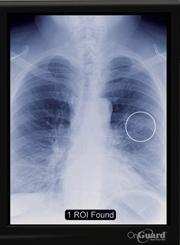

OnGuard chest X-ray CAD technology was approved by the FDA in June and offers radiologists an opportunity to effectively and consistently detect suspicious, actionable nodules that may be early-stage lung cancer. Using an existing X-ray, OnGuard places markers around regions of the lung that may be early-stage cancer.